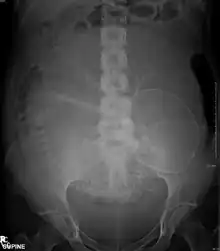

Projectional radiographs

Projectional radiography is the practice of producing two-dimensional images using X-ray radiation. Bones contain a high concentration of calcium, which, due to its relatively high atomic number, absorbs X-rays efficiently. This reduces the amount of X-rays reaching the detector in the shadow of the bones, making them clearly visible on the radiograph. The lungs and trapped gas also show up clearly because of lower absorption compared to tissue, while differences between tissue types are harder to see.[113]

Projectional radiographs are useful in the detection of pathology of the skeletal system as well as for detecting some disease processes in soft tissue. Some notable examples are the very common chest X-ray, which can be used to identify lung diseases such as pneumonia, lung cancer, or pulmonary edema, and the abdominal x-ray, which can detect bowel (or intestinal) obstruction, free air (from visceral perforations), and free fluid (in ascites). X-rays may also be used to detect pathology such as gallstones (which are rarely radiopaque) or kidney stones which are often (but not always) visible. Traditional plain X-rays are less useful in the imaging of soft tissues such as the brain or muscle. One area where projectional radiographs are used extensively is in evaluating how an orthopedic implant, such as a knee, hip or shoulder replacement, is situated in the body with respect to the surrounding bone. This can be assessed in two dimensions from plain radiographs, or it can be assessed in three dimensions if a technique called '2D to 3D registration' is used. This technique purportedly negates projection errors associated with evaluating implant position from plain radiographs.[114]